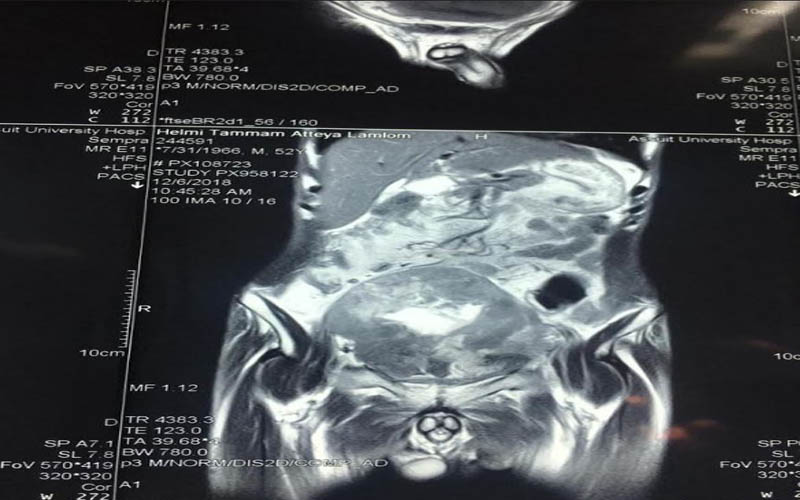

كما كشف الدكتور عمرو أبو فدان المدرس بقسم جراحة المسالك وعضو الفريق الطبي المسئول عن العملية انه فور وصول المريض إلى المستشفى تم خضوعه لعدد من الإشاعات والفحوصات الأولية والتي بينت تضخم حجم الورم مما يستلزم التدخل الجراحي لفصل الورم عن الأنسجة المحيطة وإنقاذ حياه المريض وبالفعل تم إجراء الجراحة بنجاح وخرج المريض من غرفة العمليات دون أي مضاعفات كما تم متابعة الحالة فى غرفة العناية المركزة لمدة 24 ساعة وعند استقرار حالة المريض تم نقله إلى غرفته بمستشفى جراحة المسالك البولية والكلى ، وفى السياق ذاته نوه أن نجاح العملية تم بفضل تضافر جهود الفريق الطبي بقسم جراحة المسالك البولية والكلى وعلى رأسه الدكتور حسنى البهنساوى الأستاذ المساعد بالقسم ، ومدرسين القسم وهم الدكتور أيمن عاصم ، و محمد أسامه ، وعمرو عصام ، والمعيد محمد عماد الدين ، إلى جانب فريق التخدير بقيادة الدكتور محمد أنور المدرس بقسم التخدير والعناية المركزة .

وعن تفاصيل العملية فقد أوضح الدكتور ضياء عبد الحميد الأستاذ بقسم جراحة المسالك البولية والكلى ورئيس وحدة أورام المسالك وقائد الفريق الطبي المسئول عن العملية ، أن تلك العملية تعد من أخطر عمليات استئصال أورام المثانة البولية وذلك نظراً لكبر حجم الورم واختراقه للأمعاء والأنسجة المجاورة من الشرايين والعضلات ، مما يشكل خطورة بالغة على حياه المريض والذي تم تعرضه لظروف معينة تسببت في إهماله للمرض لعدة سنوات ، مشيراً أن ذلك تم من خلال التنسيق والتعاون مع أعضاء قسم الجراحة العامة .